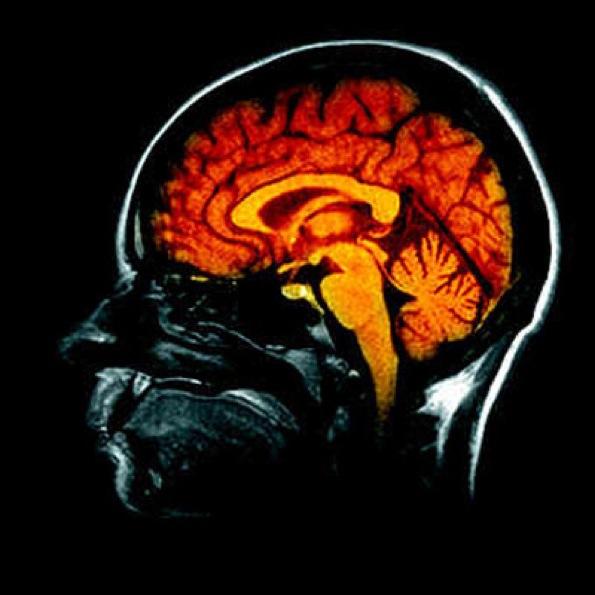

Le fonctionnement de notre cerveau est absolument passionnant... il gouverne toutes nos actions, vous le saviez déjà ! mais ce qui est plus étonnant, c'est que notre corps réagit aux actions... qu'elles soient réellement ou non effectuées !.